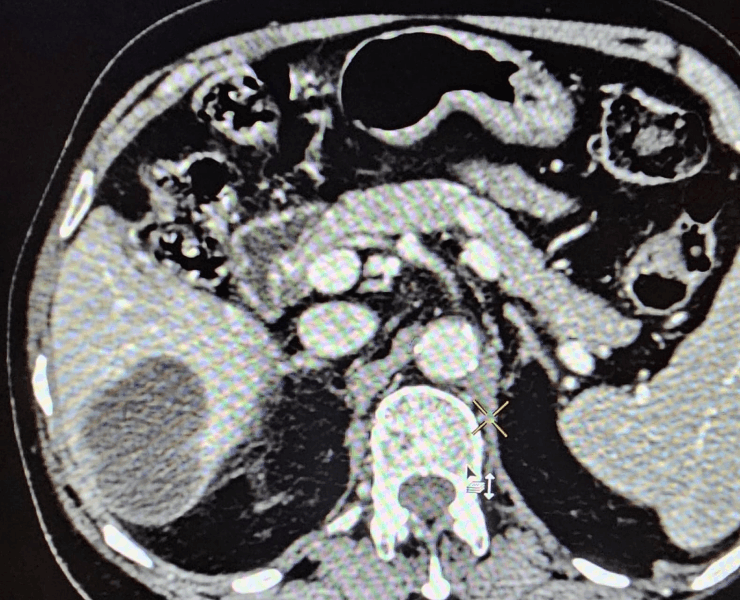

- Thermal ablation (radiofrequency or microwave): destroys tumour tissue by heating it from within through a thin needle placed under USG/CT guidance.

Microwave ablation of liver cancers

Many cancerous tumours of the kidney, especially small or localised lesions, can be treated by thermal ablation techniques rather than open surgery, depending on patient profile and tumour characteristics.

- Radiofrequency ablation (RFA): uses controlled radiofrequency energy to heat and destroy the tumour via a needle inserted through the skin.

- Microwave ablation: delivers microwave energy to achieve rapid, predictable ablation zones, often suitable for selected renal tumours.

- Procedures are performed under USG/CT guidance to precisely target the lesion while preserving as much normal kidney tissue as possible.

Kidney cancer treatment by Microwave Ablation method